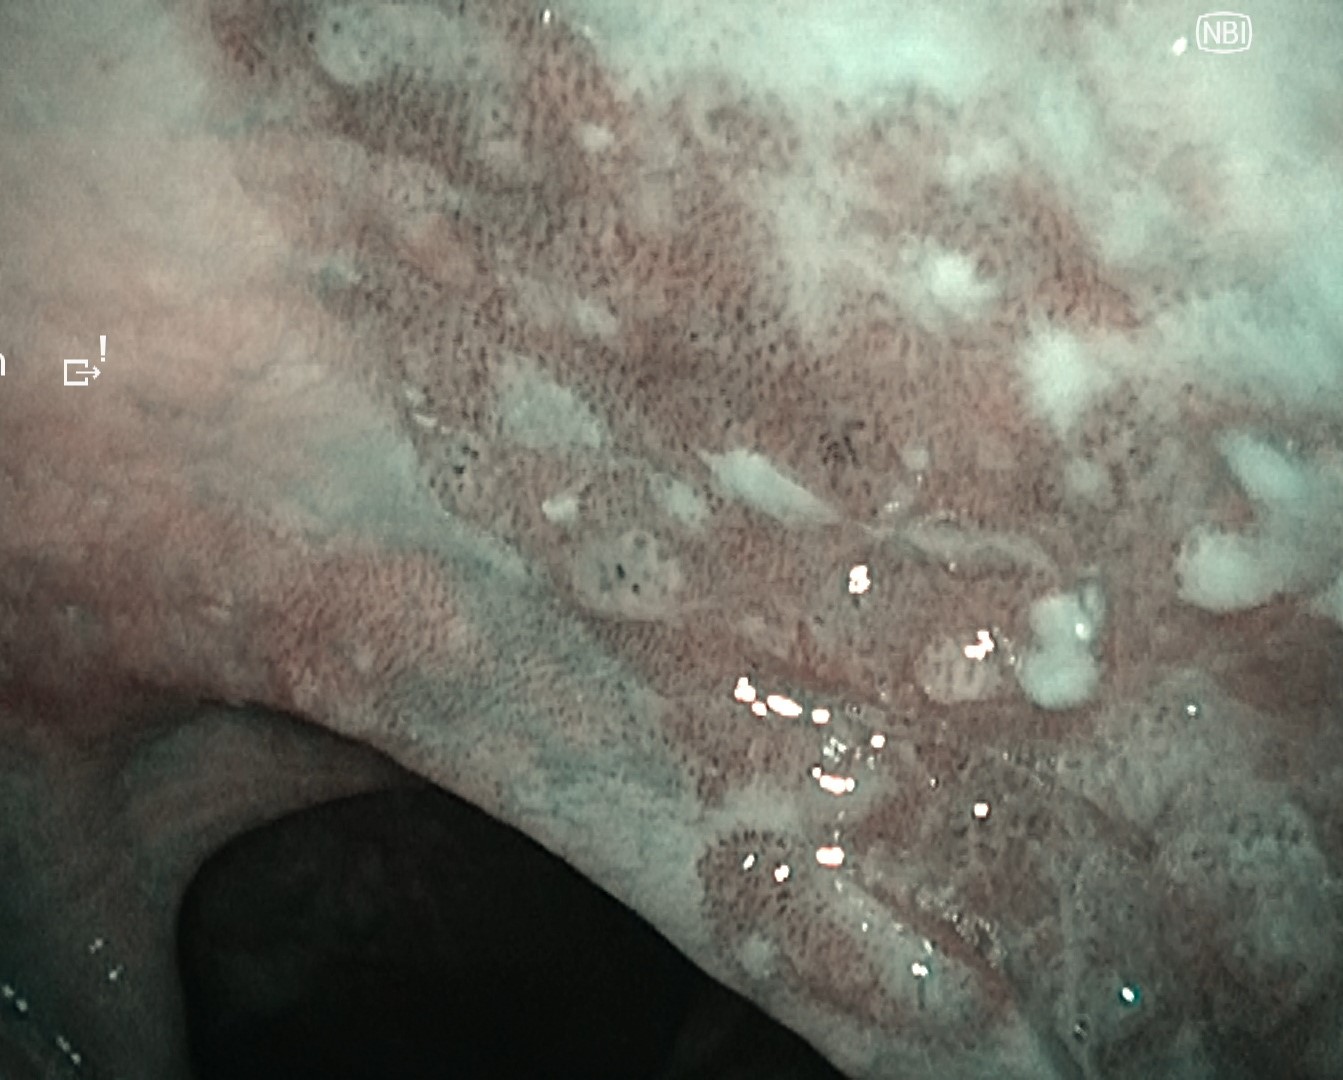

Case 3: Hypopharyngeal High-Grade Dysplasia

Under general anesthesia, the left pyriform sinus was observed after hypopharyngeal exposure. A well-defined brownish area with atypical microvessels was identified.

Compared with VISERA ELITE OTV-S190, VISERA S OTV-S500 demonstrated reduced color and luminance unevenness due to noise reduction processing, improved depth of field, and sharper edge definition, resulting in clearer visualization of the lesion.

NBI Image

Video System Center: VISERA S OTV-S500

Video Rhinolaryngoscope: ENF-VH